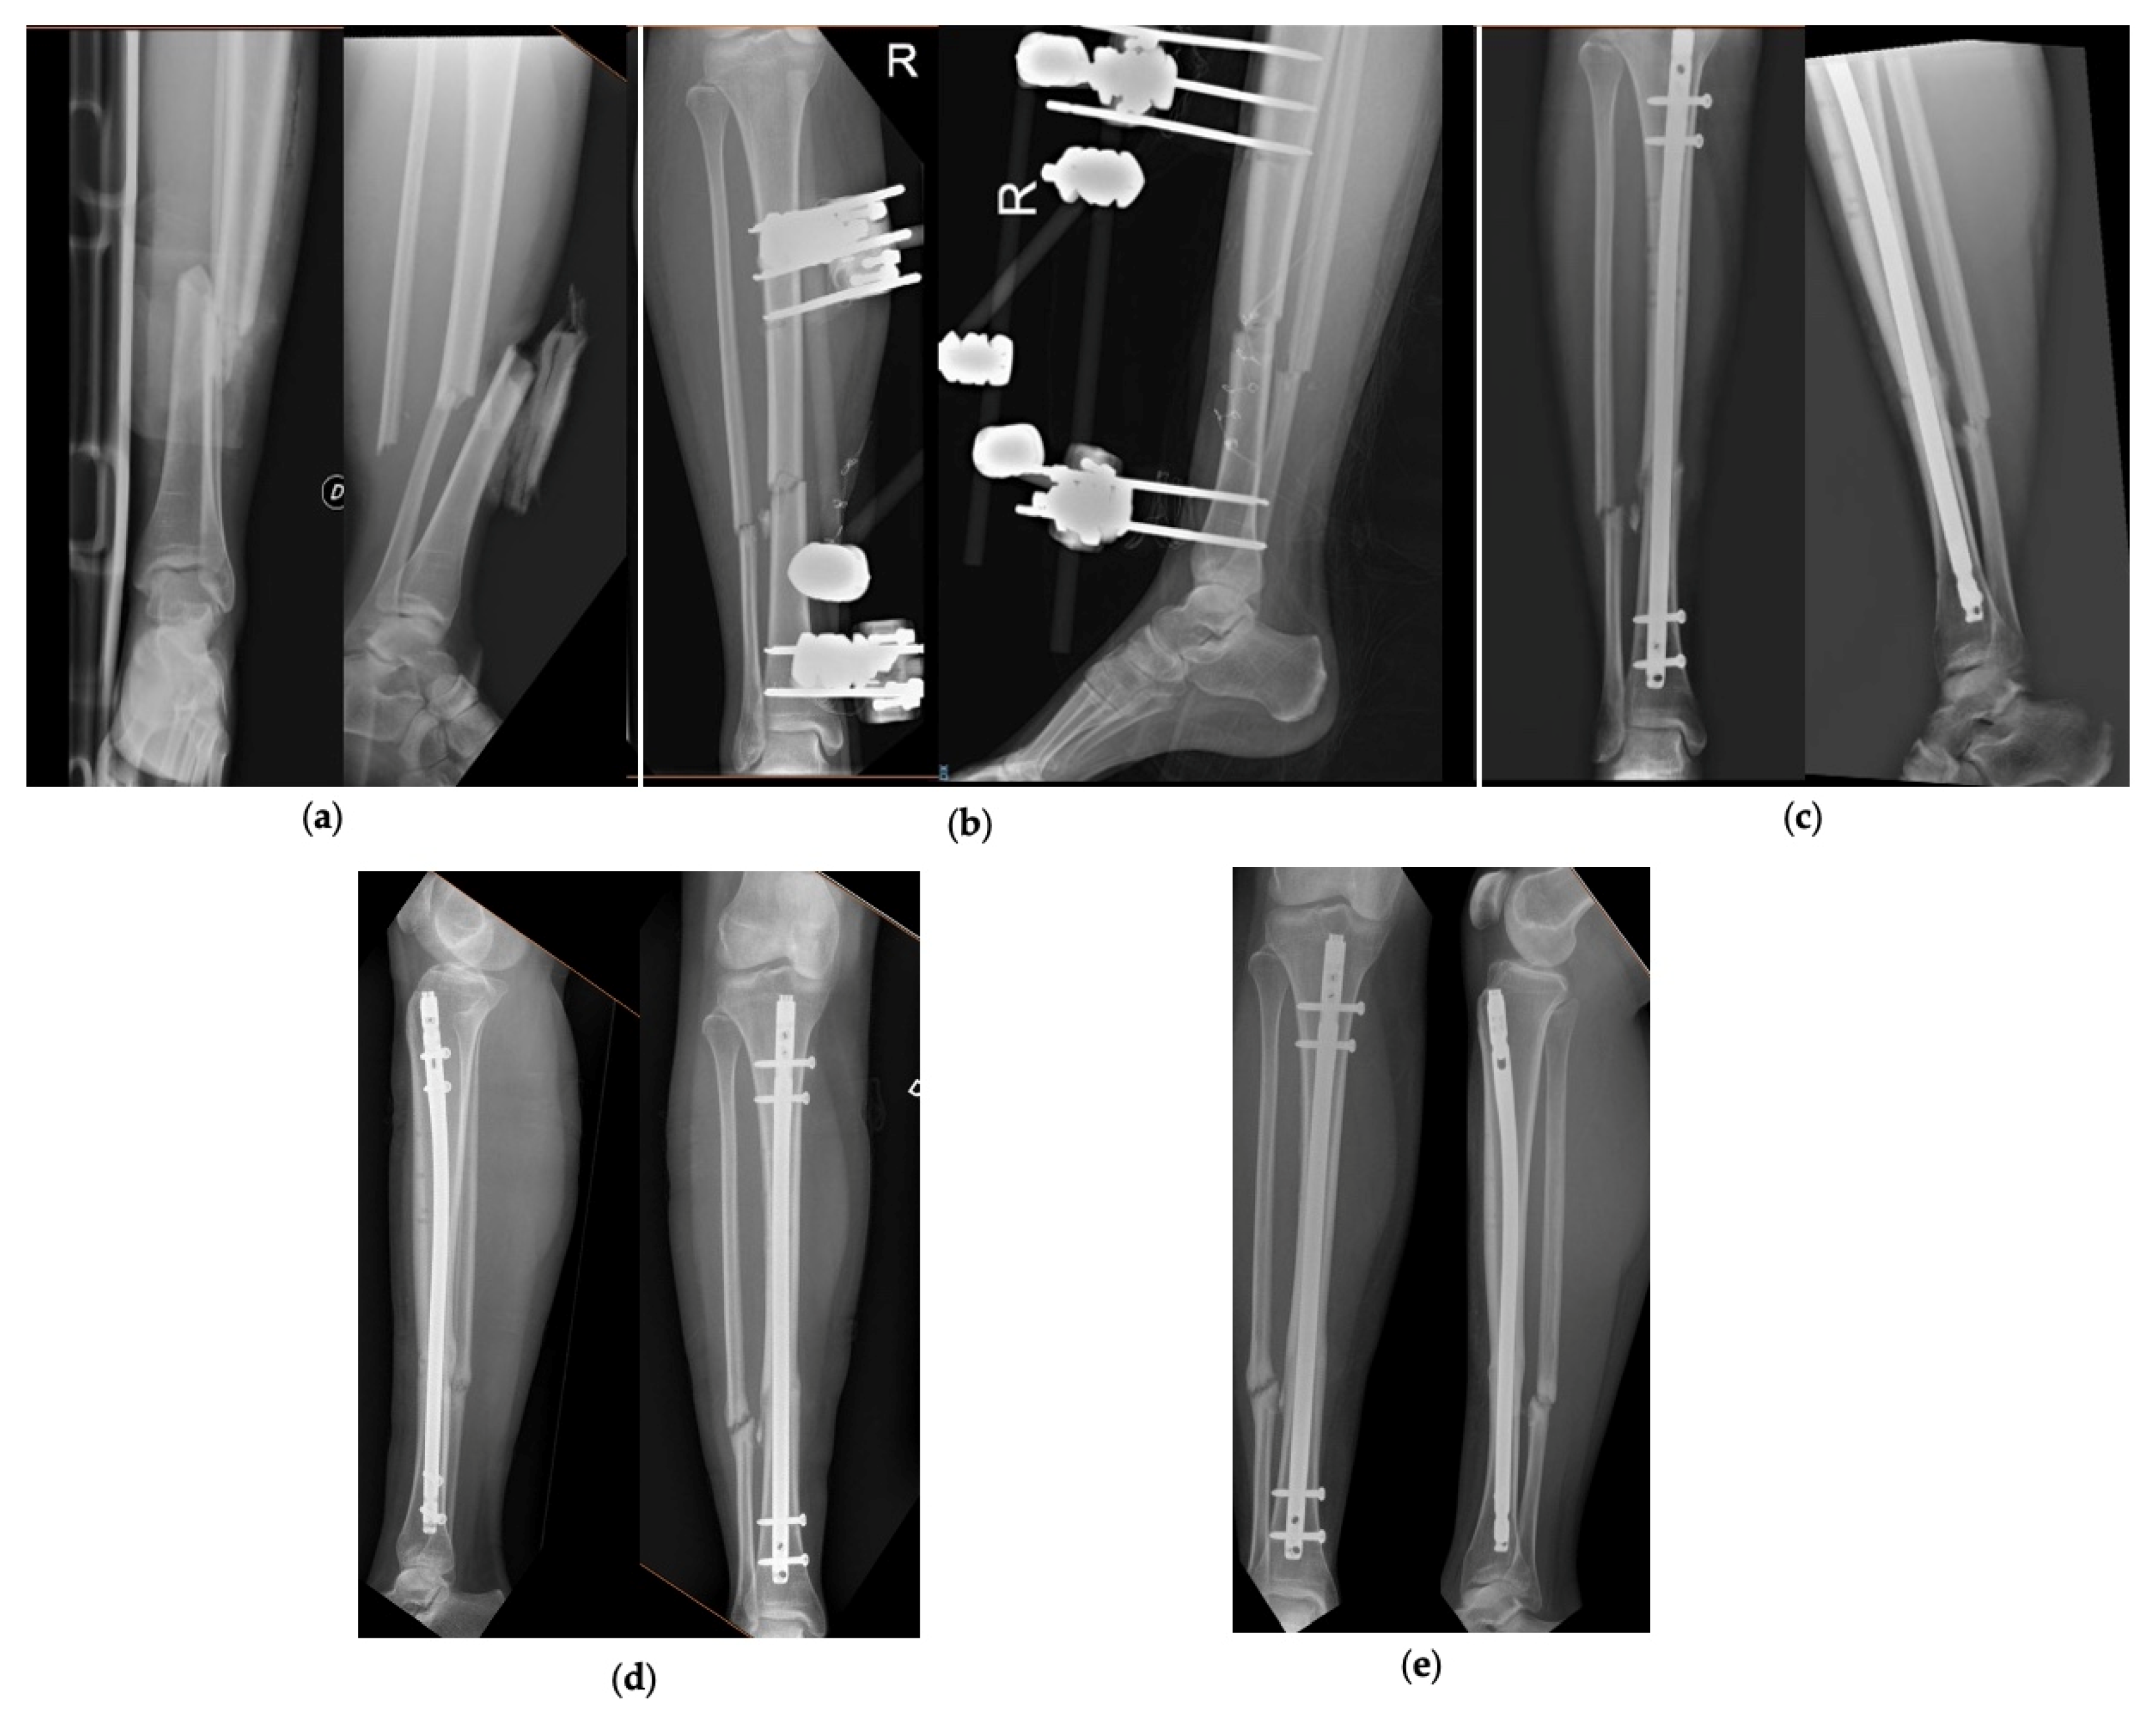

Figure 2 and Figure 3 show 2 clinical cases of the series, with pre-operative and follow-up radiographic images.

Figure 3.

Patient number 31 of the series. (a) Pre-operative AP and LL X-rays, (b) AP and LL X-ray after application of the external fixator, (c) AP and LL X-rays at 3 months, (d) AP and LL X-rays at 6 months, (e) AP and LL X-rays at 12 months.